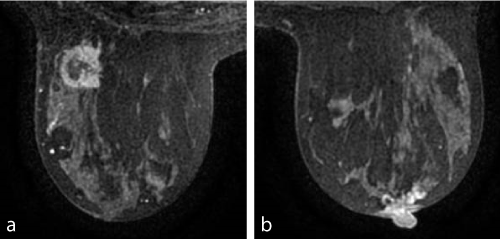

Case 5

a:      12-mm lobulated mass suggestive of IDCa.

b:      6-mm lobulated mass suggestive of IDCa. Pathology: 24-mm IDCa.

Case 6

a:      33-mm mass suggestive of IDCa or extensive intraductal carcinoma.

b:      Stippled enhancement suggestive of DCIS. Pathology: 24-mm apocrine carcinoma.